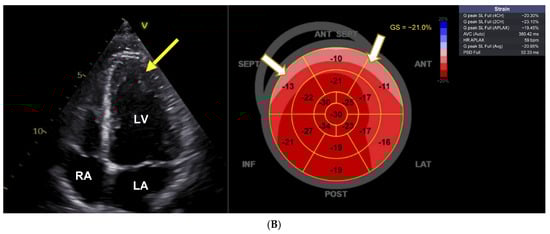

NT-proBNP was 226 ng/L (normal < 121 ng/L), there were no signs of pheochromocytoma, and renal function was normal. She had no cardiac symptoms, but there were ECG changes (Figure 2A), and transthoracic echocardiography revealed pronounced LVH and severe reduction in the LV GLS to −13%. A pharmacogenetic investigation found a CYP2D6 intermediate metabolizer phenotype (AS 1.0, genotype *1/*4.001) IM, and CYP2C19 ultrarapid metabolizer phenotype (genotype *17/*17). VEN dose was reduced to 37.5 mg/day as the patient refused to stop it completely, and under the reduced dose serum concentrations were low-normal (VEN 0.12 µmol/L; O-desmethyl-VEN 0.31 µmol/L, and VEN + O-desmethyl-VEN 0.43 µmol/L (normal 0.36–1.44 µmol/L)). Subsequently, the ECG normalized, and echocardiographic abnormalities regressed (Figure 2B). Cardiac evaluation in November 2024 under Venlafaxine 75 mg shows regression of LV-hypertrophy (yellow arrows), a LVEF of 54%, and an improvement in the LV strain (−16.2%).

Figure 2.

Reversible hypertrophic cardiomyopathy after dose reduction. (A) ECG and echocardiography with pronounced changes resembling hypertrophic cardiomyopathy. First cardiac evaluation, May 2023. The ECG shows normal sinus rhythm with a QTc interval of 455ms and negative T-waves resembling HCM (red arrows). Transthoracic echocardiography during therapy with venlafaxine 150 mg shows severe left ventricular hypertrophy (yellow arrows) with a preserved left ventricular ejection fraction of 60%, and a severely diminished left ventricular global longitudinal strain of −12.9%. LV = left ventricle, LA = left atrium. (B) Reversal of ECG changes and regression left ventricular hypertrophy (yellow arrows) after 1.5 years as well as improvement of left ventricular global longitudinal strain to −16.2%.